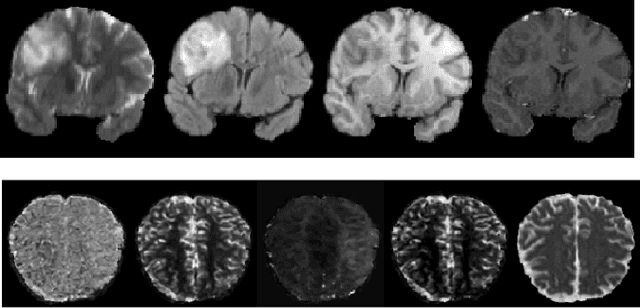

Magnetic Resonance Imaging (MRI) of the brain can come in the form of different modalities such as T1-weighted and Fluid Attenuated Inversion Recovery (FLAIR) which has been used to investigate a wide range of neurological disorders. Current state-of-the-art models for brain tissue segmentation and disease classification require multiple modalities for training and inference. However, the acquisition of all of these modalities are expensive, time-consuming, inconvenient and the required modalities are often not available. As a result, these datasets contain large amounts of \emph{unpaired} data, where examples in the dataset do not contain all modalities. On the other hand, there is smaller fraction of examples that contain all modalities (\emph{paired} data) and furthermore each modality is high dimensional when compared to number of datapoints. In this work, we develop a method to address these issues with semi-supervised learning in translating between two neuroimaging modalities. Our proposed model, Semi-Supervised Adversarial CycleGAN (SSA-CGAN), uses an adversarial loss to learn from \emph{unpaired} data points, cycle loss to enforce consistent reconstructions of the mappings and another adversarial loss to take advantage of \emph{paired} data points. Our experiments demonstrate that our proposed framework produces an improvement in reconstruction error and reduced variance for the pairwise translation of multiple modalities and is more robust to thermal noise when compared to existing methods.